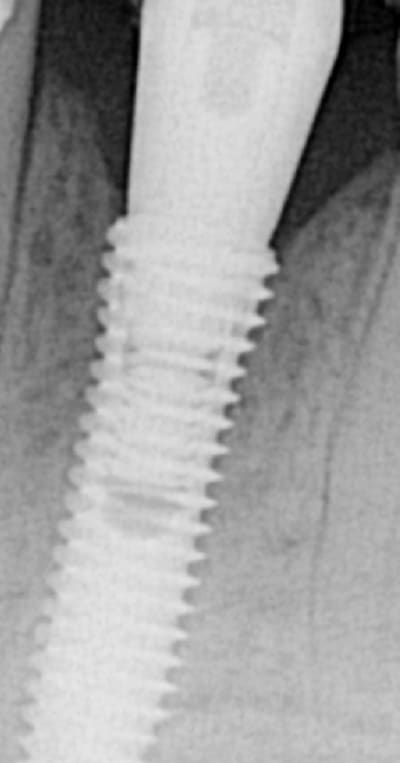

EII et Mise en vitrine immédiate, ici implant très enfoui, premier cliché à 3 mois post-op puis à un an (il faut préciser que le contrôle de plaque est plus que parfaitement réalisé par le patient).

(implant Dentium superline avec état de surface SLA)